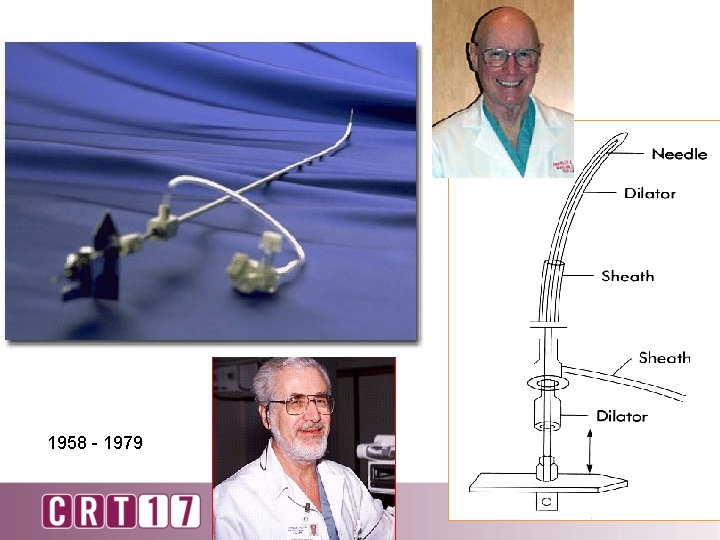

1958 - 1979